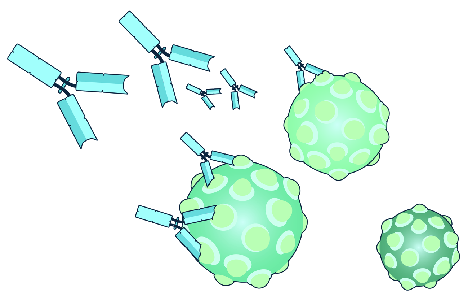

Detailreiche Fotografien aus der medizinischen Praxis ergänzen die Texte; moderne, genaue,

wissenschaftliche Zeichnungen geben Einblick in die Anatomie und die Funktion der Lunge und

anderer Organe.